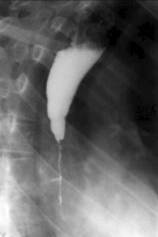

Cardiospasmul

Este o stare de contractura a jonctiunii esogastrice care īntrerupe complet tranzitul. El este produs de un reflex local sau la distanta.

Portiunea terminala a esofagului este īngustata axial cu contururi netede. Esofagul supraiacent este dilatat uneori foarte mult. Umplerea se face de jos īn sus. Exista lichid de staza. Undele peristaltice sunt vii, frecvente dar ineficiente. Staza esofagiana dureaza 3-4 ore. Cardia se destinde la un moment dat producāndu-se evacuarea īntregului continut esofagian (legea totul sau nimic). Aceasta particularitate a evacuarii esofagului diferentiaza cardiospasmul de achalazie.